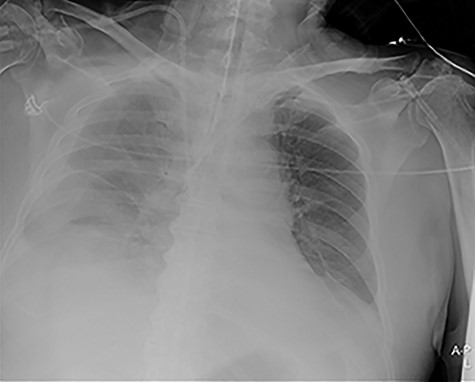

Our surgical team was contacted after 4 h, as the pleural fluid had become grossly haemorrhagic. A CXR showed haemothorax (Fig. 2). Upon clinical deterioration, the patient was intubated, and a 24Ch chest tube was introduced. Approximately, 500 ml of blood was immediately drained, followed by 300 ml during the first 30 min. ICA laceration was suspected. Despite transfusion of red blood cells and plasma and infusion of noradrenaline, the patient remained circulatory unstable. A new CXR showed massive haemothorax despite drainage (Fig. 3). The patient was now utterly haemodynamically unstable and not suited for transportation. As there are no thoracic surgeons or interventional radiologists in our hospital, the general surgeons decided to take him to the operating theatre. A wide anterolateral right thoracotomy was performed with patient lying in left lateral decubitus position. The right pleural cavity was full of fresh and coagulated blood. The pulsating bleeding was seen coming from the posterolateral, caudal chest wall, but the exact site deep down in the sharp costophrenic angle could not be localized and was inaccessible for any surgical haemostatic manoeuvre.

Portable chest X-ray in half-upright position showing massive haemothorax despite chest tube.